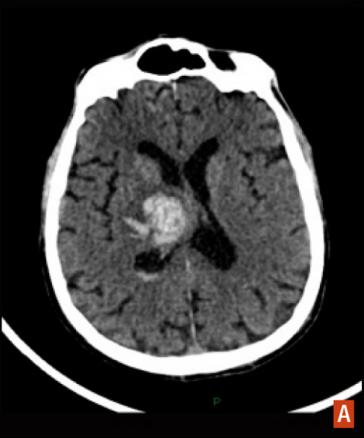

Hématome intracérébral profond

TDM cérébrale sans injection, hyperdensité spontanée.